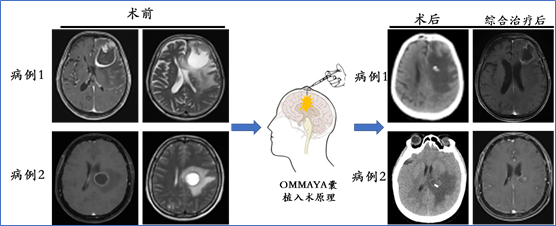

3. Ommaya囊(欧玛亚囊)植入术目的:释放肿瘤囊液,降低颅内压力、缓解症状,为后续放疗/化疗等综合治疗创造有利条件;

适应症:适用于颅内体积较大的囊性病灶;脑转移瘤引发脑积水的患者;脑膜转移患者(可选脑室内化疗)

Ommaya囊植入手术病例